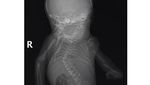

Kondisi tersebut terkait dengan sindrom tulang radial, kemungkinannya karena hernia diafragma bawaan dan / atau obstruksi usus, juga penyakit defisiensi surfaktan stadium lanjut. Bayi dengan sindrom tersebut biasanya memiliki kedua tungkai yang menyatu, seperti putri duyung. Foto: Instagram

Banyak bayi yang terlahir dengan kondisi ini tidak bertahan setelah sehari atau dua hari dilahirkan karena banyaknya komplikasi yang terjadi. Yang sering ditemukan seperti ketidaknormalan pada sistem pencernaan, tulang pelvis, ginjal yang belum matang, sampai malformasi jantung. Foto: Instagram